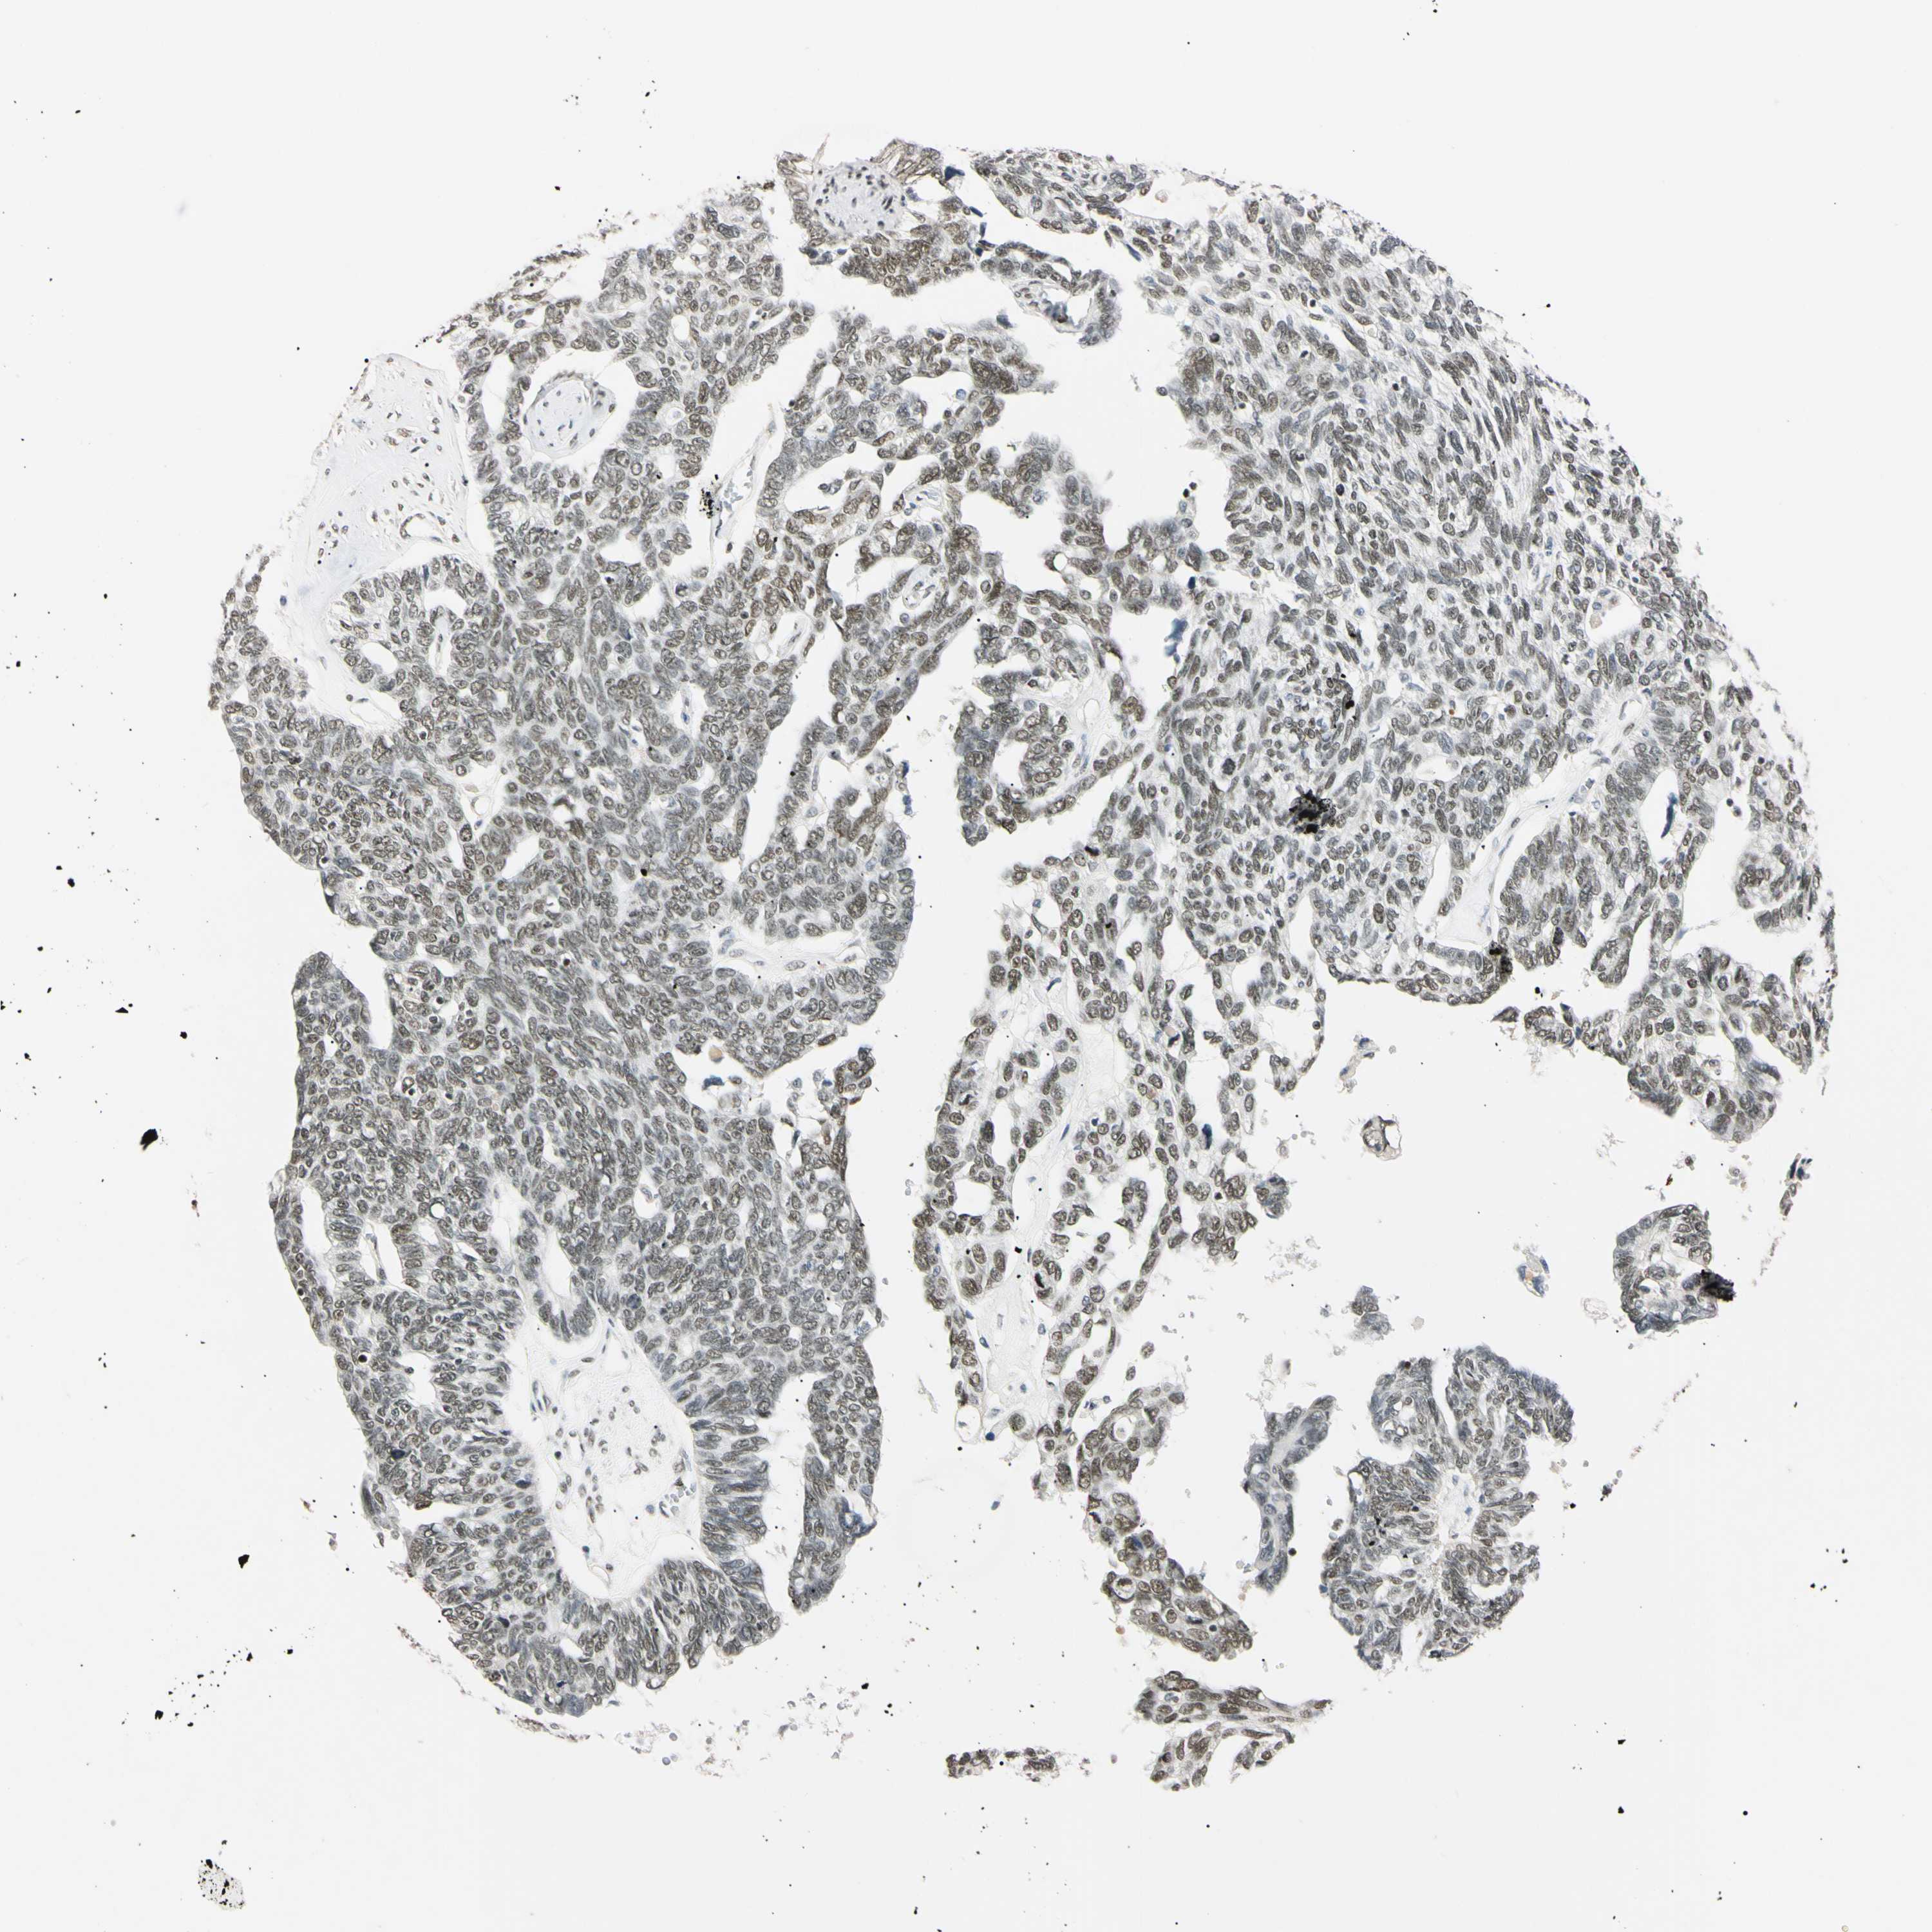

OVARIAN CANCER - Protein expressioni

A mouse-over function shows sample information and annotation data. Click on an image to view it in a full screen mode. Samples can be filtered based on level of antibody staining by selecting one or several of the following categories: high, medium, low and not detected. The assay and annotation is described here.

Note that samples used for immunohistochemistry by the Human Protein Atlas do not correspond to samples in the TCGA dataset.

Antibody stainingi

Antibody staining in the annotated cell types in the current human tissue is reported as not detected, low, medium, or high, based on conventional immunohistochemistry profiling in selected tissues. This score is based on the combination of the staining intensity and fraction of stained cells.

Each image is clickable and will lead to virtual microscopy that enables deeper exploration of all samples and also displays staining intensity scores, fraction scores and subcellular localization as well as patient and tissue information for each sample.

Antibody HPA008751

Cystadenocarcinoma, serous, NOS